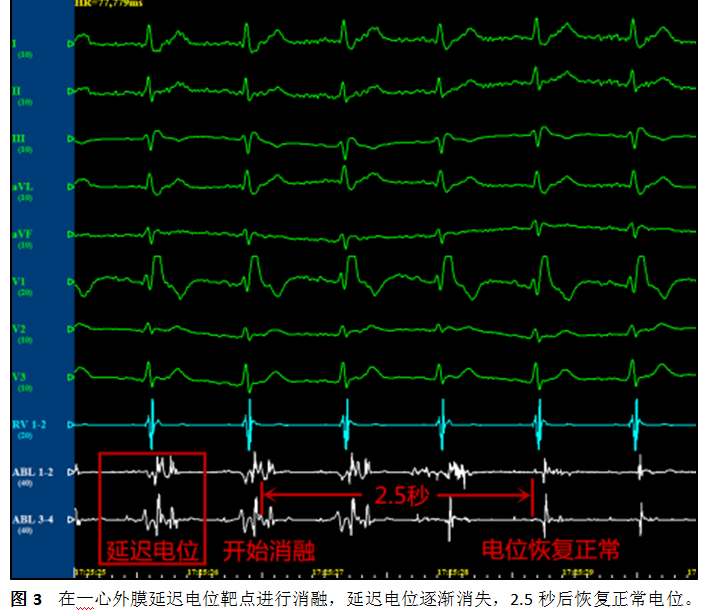

殷跃辉教授仔细回顾患者病历资料,发现触发患者室速发作的室性早搏符合右室流出道起源特点(图1B),提示该区域存在电活动异常。综合患者医疗、社会、心理等各方面情况,结合科室在心律失常领域的突出优势,经过反复论证后,殷跃辉教授建议患者尝试射频消融手术。他指出,与常规心内膜消融方法不同,Brugada综合征患者延迟电位主要分布在心外膜,必须通过干性心包穿刺,于心外膜标测消融才能取得良好效果。心外膜消融技术难度高,全国仅有少数中心可以开展,2020年1月7日,经殷跃辉教授指导,凌智瑜副教授、杜华安与陈伟杰博士于江南院区介入手术室顺利为患者完成干性心包穿刺,随后于右室流出道前壁心外膜区域标测到片状延迟电位区域,而心内膜面并未记录到异常电位(图2),完全符合术前推测。凌智瑜副教授于延迟电位区域仔细消融,每个靶点的延迟电位在数秒内即可消失(图3),整个手术过程持续3小时左右,消融完成后再次标测未见异常电位存在。术后患者恢复良好,心电图显示 Brugada波幅度明显降低(图1C)持续心电监护未见室性心律失常发作。